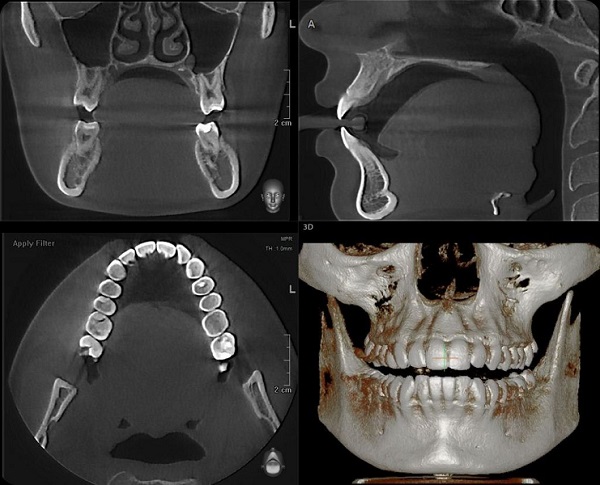

Курс ориентирован на широкую аудиторию: студенты стоматологических факультетов 3-5 курсов, клинические ординаторы, аспиранты, практикующие врачи-стоматологи, врачи-оториноларингологи. МООК направлен на теоретическую подготовку обучающихся и практикующих врачей к работе с 3д рентгенологическим исследованием-КЛКТ. Курс помимо теоретической базы содержит включение практико-ориентированных иллюстративных заданий, направленных на тренировку практической работы. В задачи курса входит полное ознакомление с неограниченными возможностями КЛКТ для диагностики патологий челюстно-лицевой области.

После освоения данного курса учащиеся, слушатели, смогут сразу применить полученные знания в своей клинической практике, усовершенствовав её, а также оптимизировать подход в работе с пациентом на диагностических этапах.